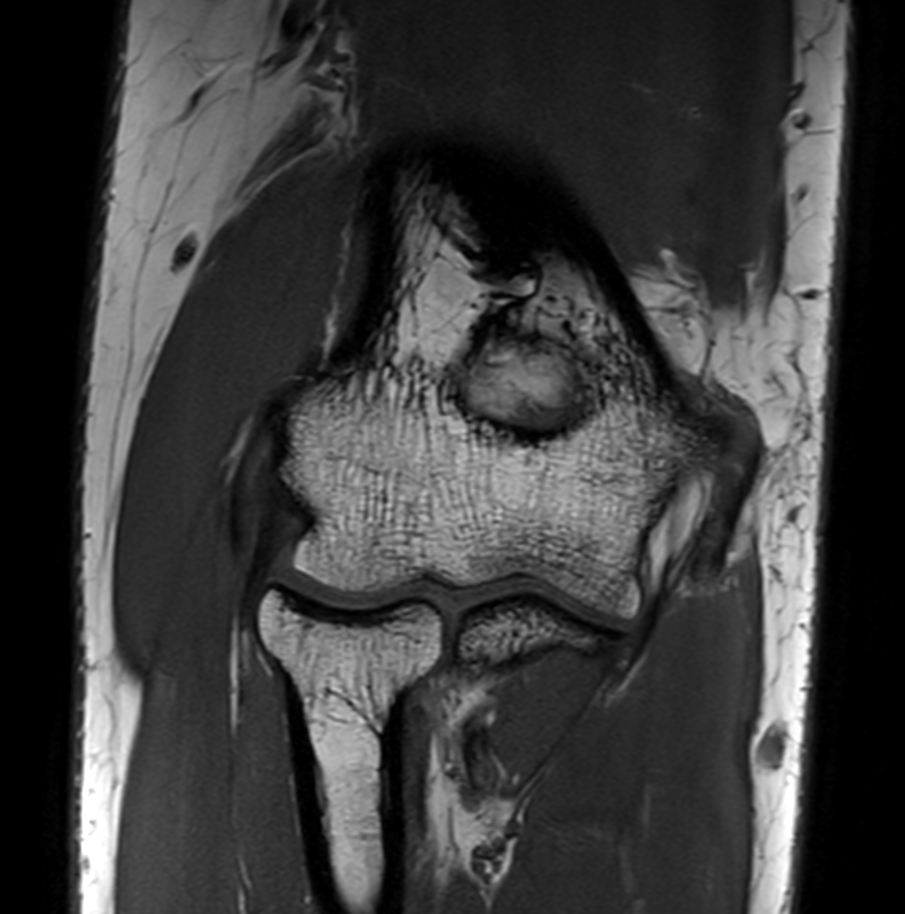

Coronal T1w TSE